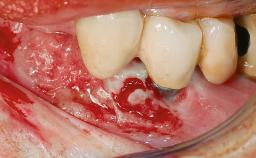

In 2004, the patient, a smoker, began dental treatment at the ACTA graduate clinic. She was a TV producer exposed to a lot of stress in her job and had a sick husband. Her maxillary teeth had been extracted, as had the mandibular canines, premolars, and molars, with the exception of tooth 34. She received a complete maxillary denture and a mandibular skeleton denture. In October 2007, her maxilla was augmented by an oral and maxillofacial surgeon; in March 2008, implants (Biomet 3i, Palm Beach, Florida, USA) were inserted at that same clinic. In 2008, the patient was presented at the Department of Oral Implantology and Prosthetic Dentistry to request restorations for her implants. An implant-supported overdenture was planned. She also asked if we could restore her occlusion with fixed prosthetics.

| Bone Volume | Deficient horizontally, requiring prior grafting |